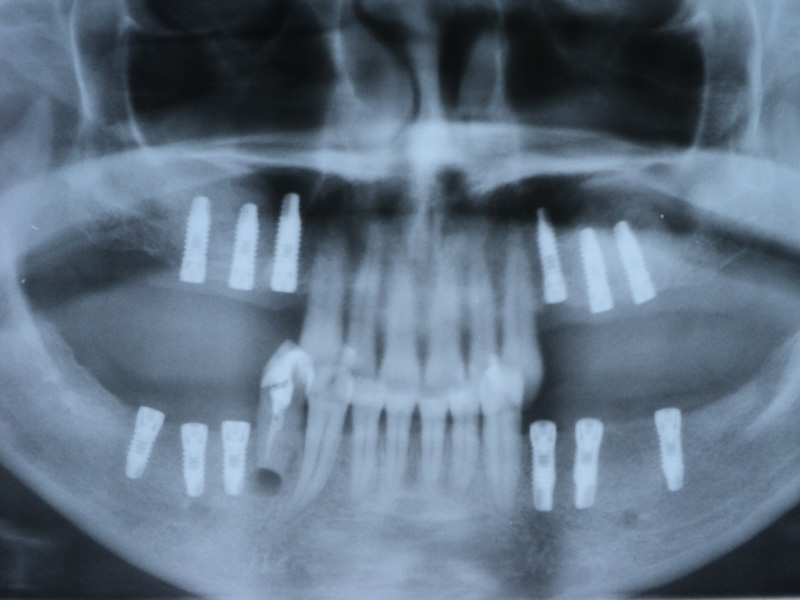

Implante - Galerie Foto

Caz I

Radio-

grafii